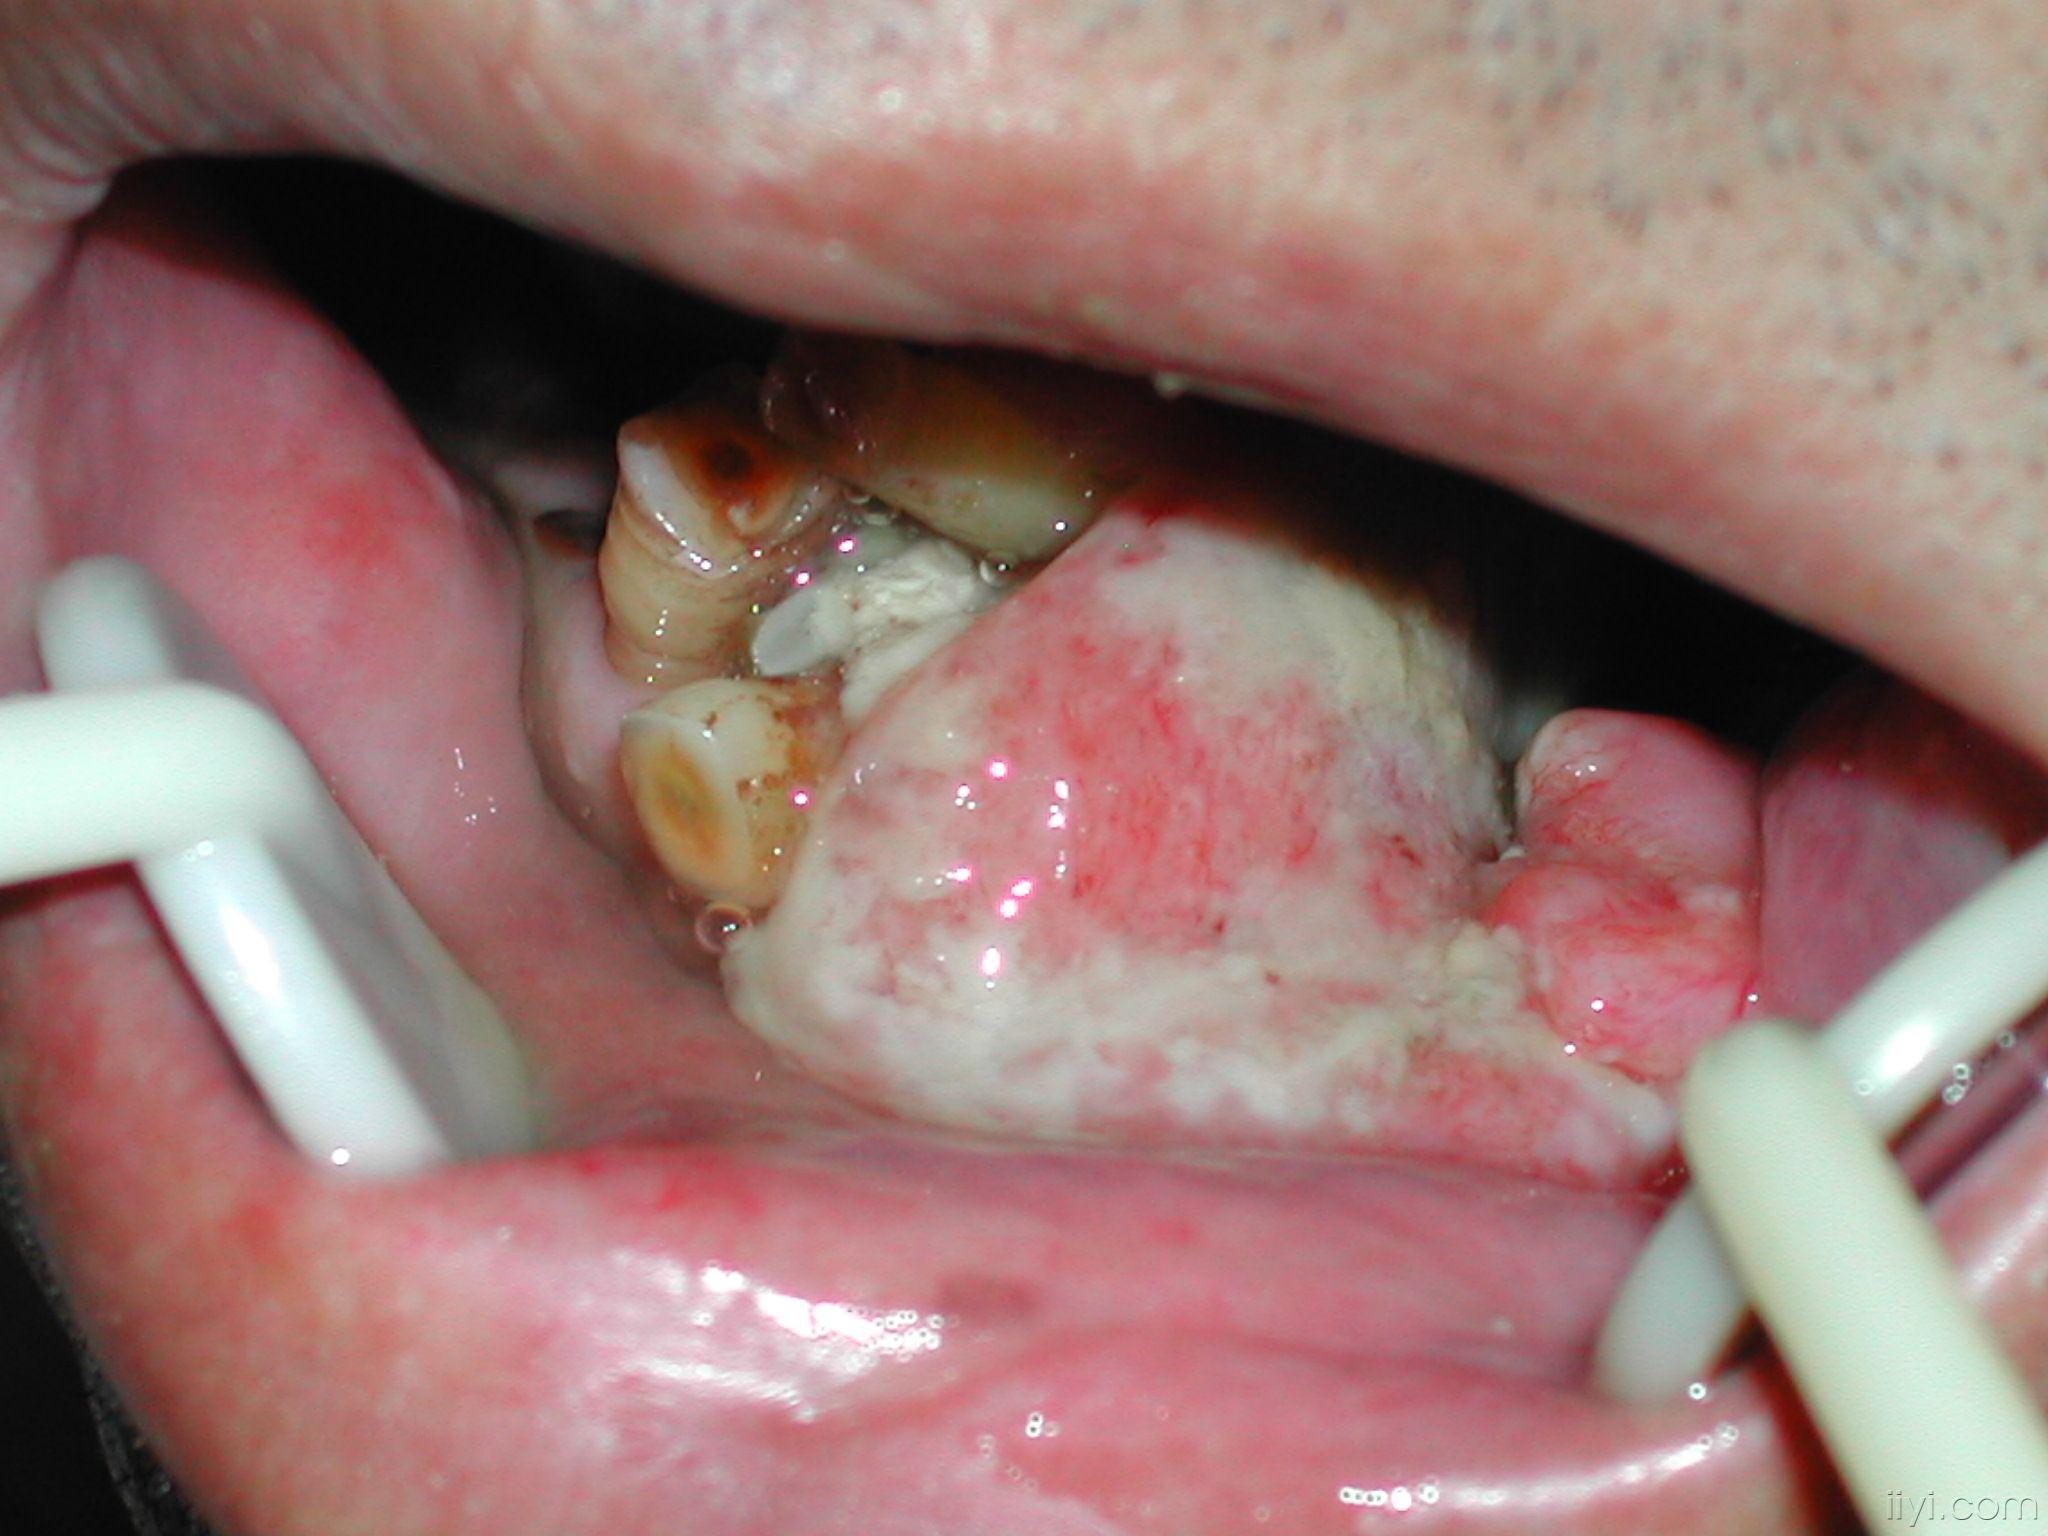

牙龈癌手术前后(图)